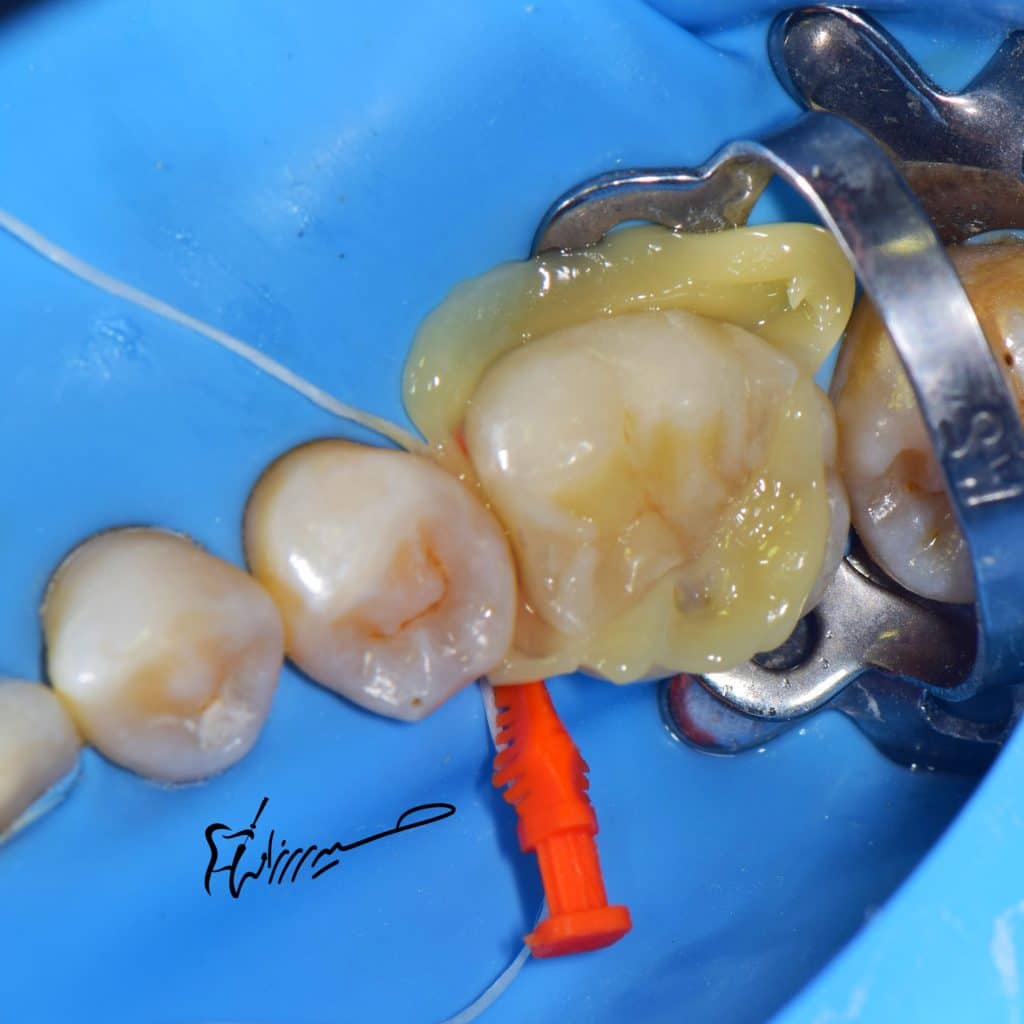

📍DME done with apx composite

📍Pre endo IDS

📍RCT

📍Cavity optimization

Preparation was air abraded with 30 micron aluminum oxide

Etching with phosphric acid

Bond application without curing

And then final cementation with heated apx composite.